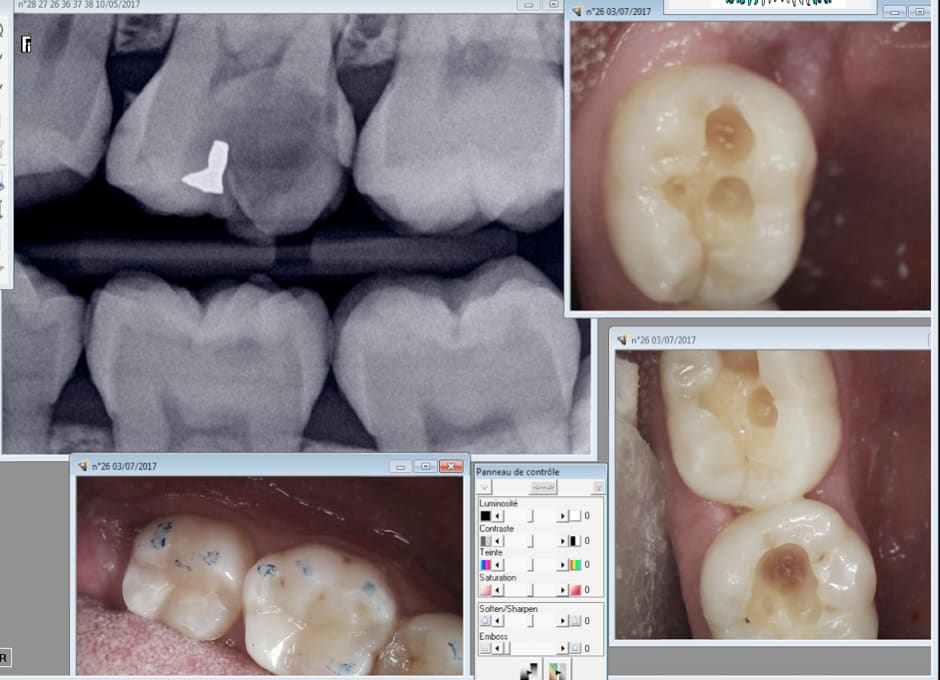

Capture d écran 2017 07 03 21.01 - Eugenol

Et ca ca vaut quoi ?

Capture d écran 2017 07 03 21.08 - Eugenol